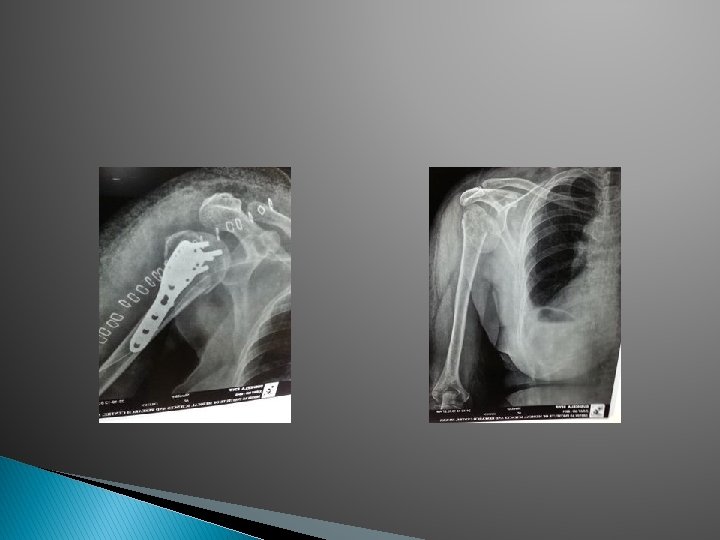

I TYPES 1. Simple 2. Compound II 1. Complete Displaced -Shift, Tilt, Rotation Un Displaced 2. Incomplete III 1. Linear Transverse Oblique Spiral - Butter Fly 2. Comminuted 3. Segmental 4. Bone Loss <50% >50%

A. O. Classification: � Ø Each long bone is numbered. First digit Bone Ø Second digit Ø Third letter AO/ASIF Segment 1– 4 Type A – C Proximal & distal A - C